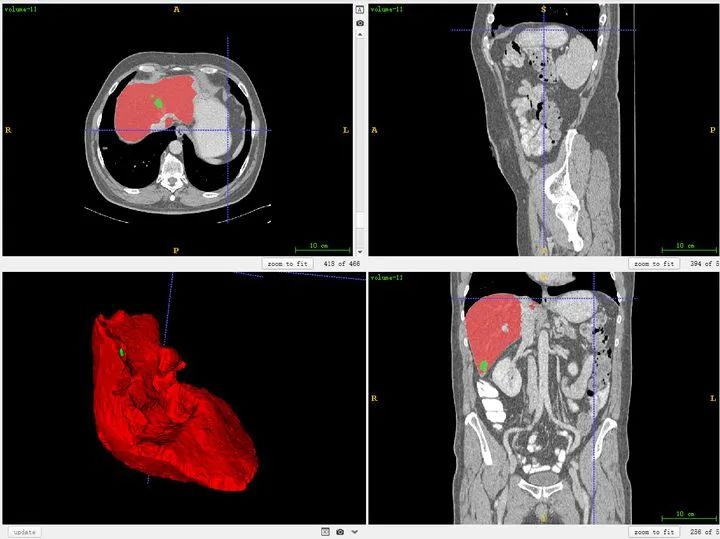

1.1 ITK-SNAP软件

首先介绍一下医学图像可视化软件ITK-SNAP, 可以作为直观感受医学图像3D结构的工具,也可以用来做为分割和检测框标注工具,免费,很好用,安利一下:ITK-SNAP官方下载地址:http://www.itksnap.org/pmwiki/pmwiki.php。此外,mangohttp://ric.uthscsa.edu/mango/是另一个非常轻量的可视化软件,也可以试试。我一般用ITK-SNAP。

也可以同时将分割结果导入,对比观察。

对于标注不太严谨的地方也可以精细化修改。当然公开集的话,绝大多数都挺好的。自己标注也是类似。(如果显示不太清晰,对比度太低,需要在软件中调节窗宽和窗位)